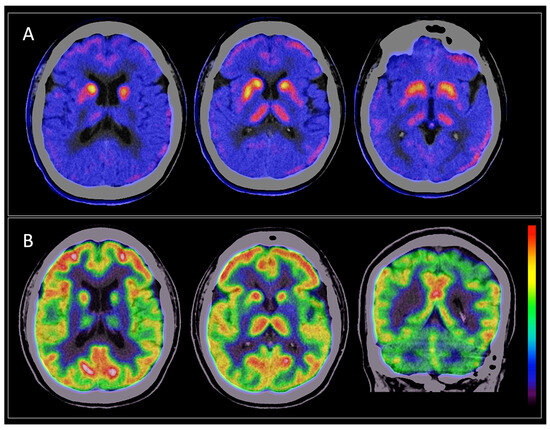

3.2. Brain [18F]DOPA PET/CT Findings

3.3. Brain [18F] FDG PET/CT Findings